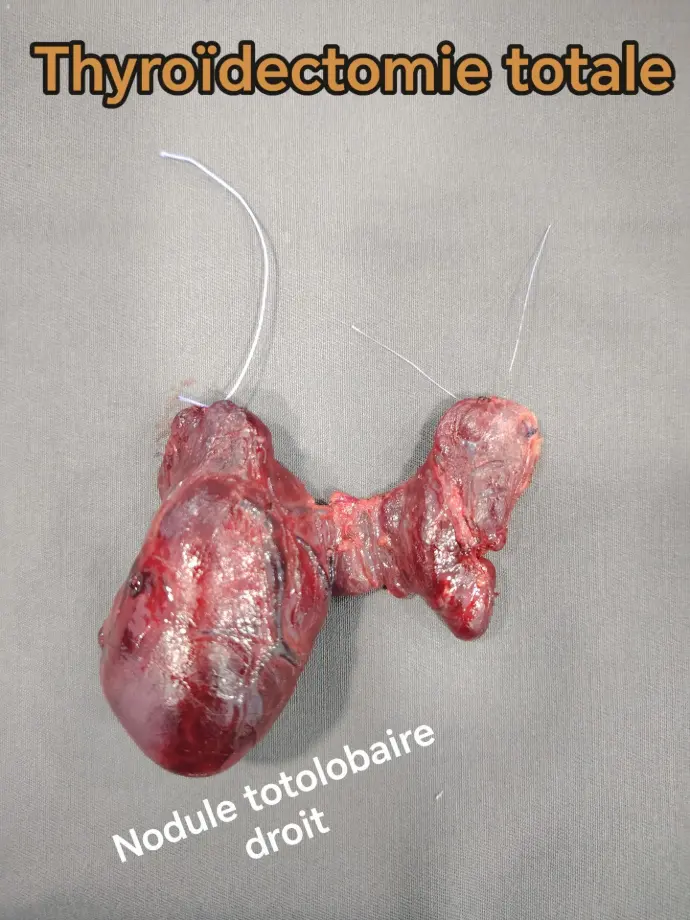

4. العقد الدرقية (Thyroid Nodules):

تكون كتل صغيرة داخل الغدة الدرقية.

غالبًا ما تكون حميدة، لكنها تحتاج إلى الفحص لاستبعاد السرطان.